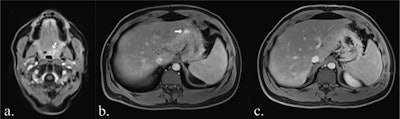

Whole-body MRI of a 39-year-old woman with LFS showing a mass in the small pelvis (white arrow) in diffusion-weighted imaging (a) and contrast-enhanced T1-weighted Dixon images (b, here: water-only image). In the coronal TIRM-sequence (c), the mass is visible, but difficult to differentiate from the intestine, emphasizing the value of diffusion-weighted imaging. Histology revealed a leiomyosarcoma.

Whole-body MRI of a 39-year-old woman with LFS showing a mass in the small pelvis (white arrow) in diffusion-weighted imaging (a) and contrast-enhanced T1-weighted Dixon images (b, here: water-only image). In the coronal TIRM-sequence (c), the mass is visible, but difficult to differentiate from the intestine, emphasizing the value of diffusion-weighted imaging. Histology revealed a leiomyosarcoma.